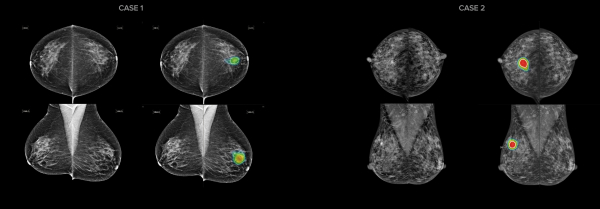

또한 병원은 유방암을 96% 정확도로 검출해 의료진의 진단을 보조하는 AI 영상판독시스템인 ‘루닛 인사이트 MMG’도 함께 도입했다. 영상의학과 의사는 루닛 AI 결과를 참고해 정상 케이스를 빠르게 선별하고, 비정상 케이스의 판독에 집중할 수 있다.